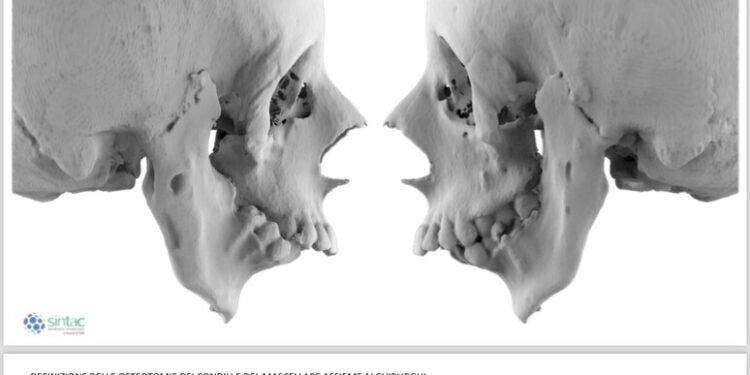

In questo caso, già nel feto si era sviluppato un ammasso osseo che aveva fuso la mandibola al cranio non consentendo l’articolazione necessaria ad aprire la bocca. Il successo dell’operazione, durata circa dieci ore, è stato il frutto di un lavoro multidisciplinare, tra le varie équipe aziendali. Oltre ai chirurghi maxillo-facciali, in sala operatoria erano presenti in venti tra colleghi chirurghi anestesisti della Rianimazione sale chirurgiche e della Chirurgia toracica. “Tuttavia – dice l’ospedale – l’intervento non si sarebbe potuto realizzare senza la piena disponibilità del direttore generale dell’azienda ospedaliero universitaria etnea, Gaetano Sirna, che ha stanziato le risorse per la realizzazione della protesi in titanio impiantata nella giovane paziente, una vera e propria opera di bioingegneria tra le più moderne. A guidare le equipes di medici e paramedici, è stata la collaborazione tra alcuni dei chirurghi maxillo facciali più esperti in Italia che ha dato vita ad una perfetta sinergia tra Nord e Sud del Paese. In particolare Alberto Bianchi, professore dell’Unità Operativa Complessa di Chirurgia Maxillo-facciale dell’Azienda Ospedaliero Universitaria “Policlinico “G. Rodolico – San Marco” e Massimo Robiony, direttore della Clinica maxillo facciale dell’ospedale universitario di Udine e il suo professore associato Salvatore Sembronio.